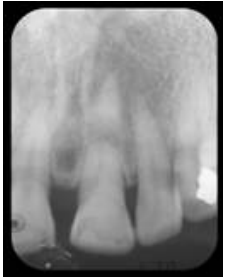

65.下圖中有何種牙齒相關的病變?

(A)Vertical root fracture (B)Horizontal root fracture (C)Dens evaginatus (D)Concussion of teeth